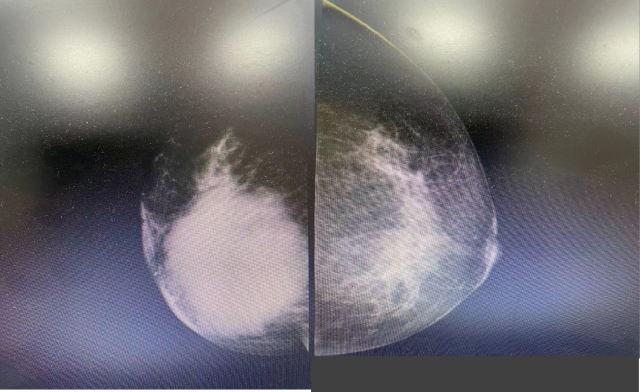

乳腺钼靶片:1 两乳少量型腺体型乳腺;2. 右乳恶性占位,BI-RADS 4c?。

乳腺钼靶片:1 两乳少量型腺体型乳腺;2. 右乳恶性占位,BI-RADS 4c?